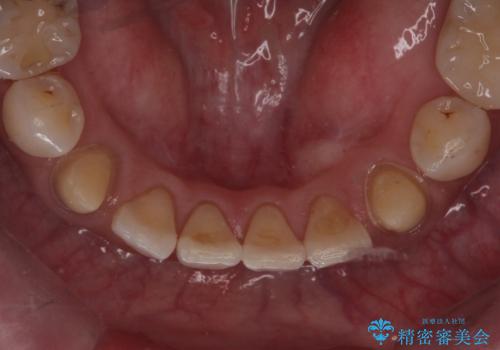

他院で矯正後、歯の神経が死んでしまった歯の治療

- 子供のころに4本抜歯してワイヤー矯正をしたとのことでした。

最近右下の犬歯の根の先付近の歯茎に何かできており、違和感があるとのでした。

CTでみたところ、下の犬歯が内側に倒れこんでおり、根の先が顎の骨から出かかっている状態でした。おそらくその影響で犬歯の神経が失活してしまったのであろうと思われます。(フェネストレーションといいます)

検査した結果下の両側の犬歯の神経が失活しており、根の治療が必要な状態でした。